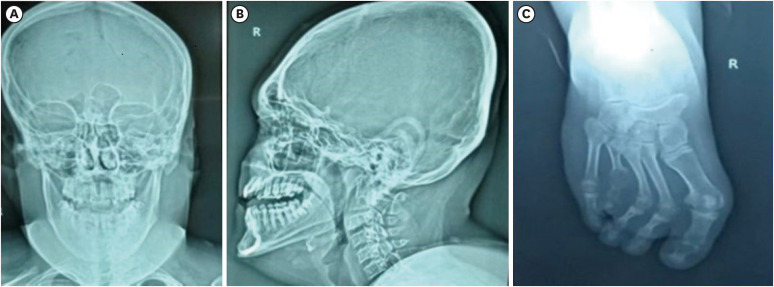

borjason - forssman - lehmann综合征(BFLS)是一种由PHF6基因突变引起的x连锁隐性疾病。该综合征的特点是身材矮小、肥胖、性腺功能减退、低张力、智力残疾、明显的面部特征、肉质耳朵、手指和脚趾异常。然而,诊断BFLS的挑战仍然是一个有趣的话题。在本病例报告中,我们介绍了一个患有BFLS的先证者的临床特征,突出了张力低下、智力残疾和独特的面部特征。虽然BFLS没有明确的治疗方法,但患者受益于从幼儿到成年的专业教育和持续监督。对症治疗,包括密切随访,可能是必要的并发症,如癫痫发作和听力问题。乳房切除术或睾酮替代疗法可根据具体情况考虑。应向受x连锁影响的家庭提供遗传咨询。

Borjeson-Forssman-Lehmann syndrome (BFLS) is an X-linked recessive disorder resulting from mutations in the PHF6 gene. The syndrome is characterized by short stature, obesity, hypogonadism, hypotonia, intellectual disability, distinctive facial features, fleshy ears, and finger and toe abnormalities. However, the diagnostic challenge in identifying BFLS remains a topic of interest. In this case report, we present the clinical characteristics of a proband with BFLS, highlighting the additional features of hypotonia, intellectual disability, and distinctive facial features. While no definitive treatment exists for BFLS, patients benefit from specialized education and ongoing supervision from early childhood through adulthood. Symptomatic treatment, including close follow-up, may be necessary for complications such as seizures and hearing problems. Mastectomy or testosterone replacement therapy may be considered on a case-by-case basis. Genetic counseling for X-linkage should be offered to affected families.